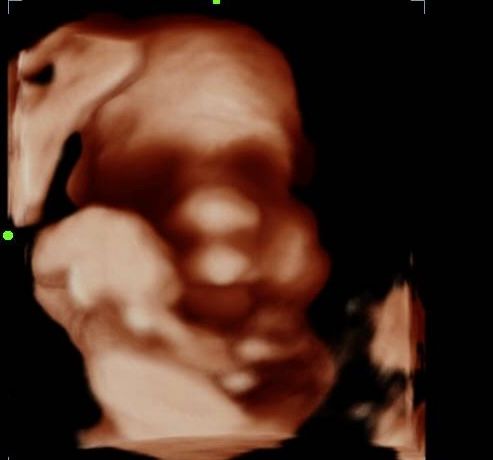

2d, 3d,4d & HD live

Enjoy a private, affordable ultrasound from the comfort of your home, perfect for moms between 7–41 weeks. Share the moment with loved ones by connecting directly to your TV for real-time viewing in 2D, 3D, or 4D. Ideal for baby showers or gender reveal parties!